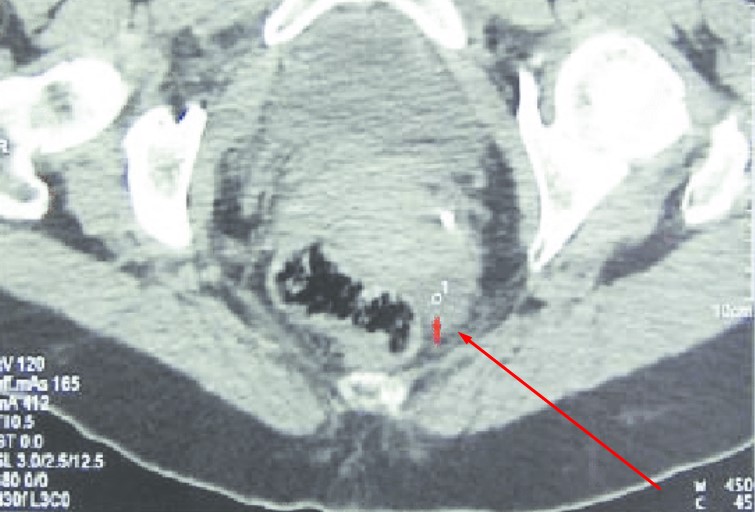

Douglas boşluğunda sıvı birikmesi durumu genellikle kadın doğum hekimine başvuran hastaların ultrason yöntemi ile muayenesi esnasında tespit edilmektedir. Bu alanda biriken sıvı elle yapılan fizik muayenelerde kolayca tespit edilemez.

Genelde ultrason yöntemiyle tespit edilse de BT gibi ileri görüntüleme tetkiklerinde de bu sıvı görülebilmektedir. Douglasta sıvı artışı yeteri kadar olduğunda ultrasonda rahatlıkla teşhis edilir.